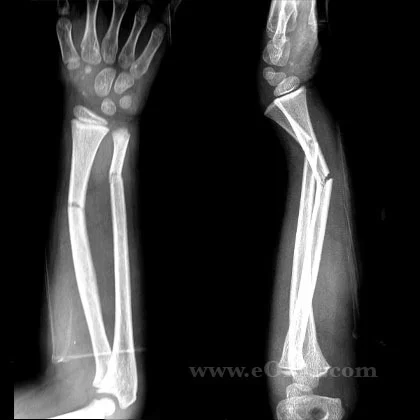

Classification by Fracture Line

- According to fracture line:

-

Complete (usual)

- Cortex fractured on both sides

Incomplete (in children)

- Green stick / Torus, Buckle /Deformation

Classification by Fracture Pattern

- According to fracture pattern:

- Simple

- Wedge comminuted

- Complex comminuted

- Multi-fragmented

Fracture Pattern and Mechanism of Force

- Fracture pattern suggests mechanism of force

- Spiral: (twisting)

- Short oblique: (compression)

- Wedge: (compression + bending)

- Transverse: (angulation) (avulsion)